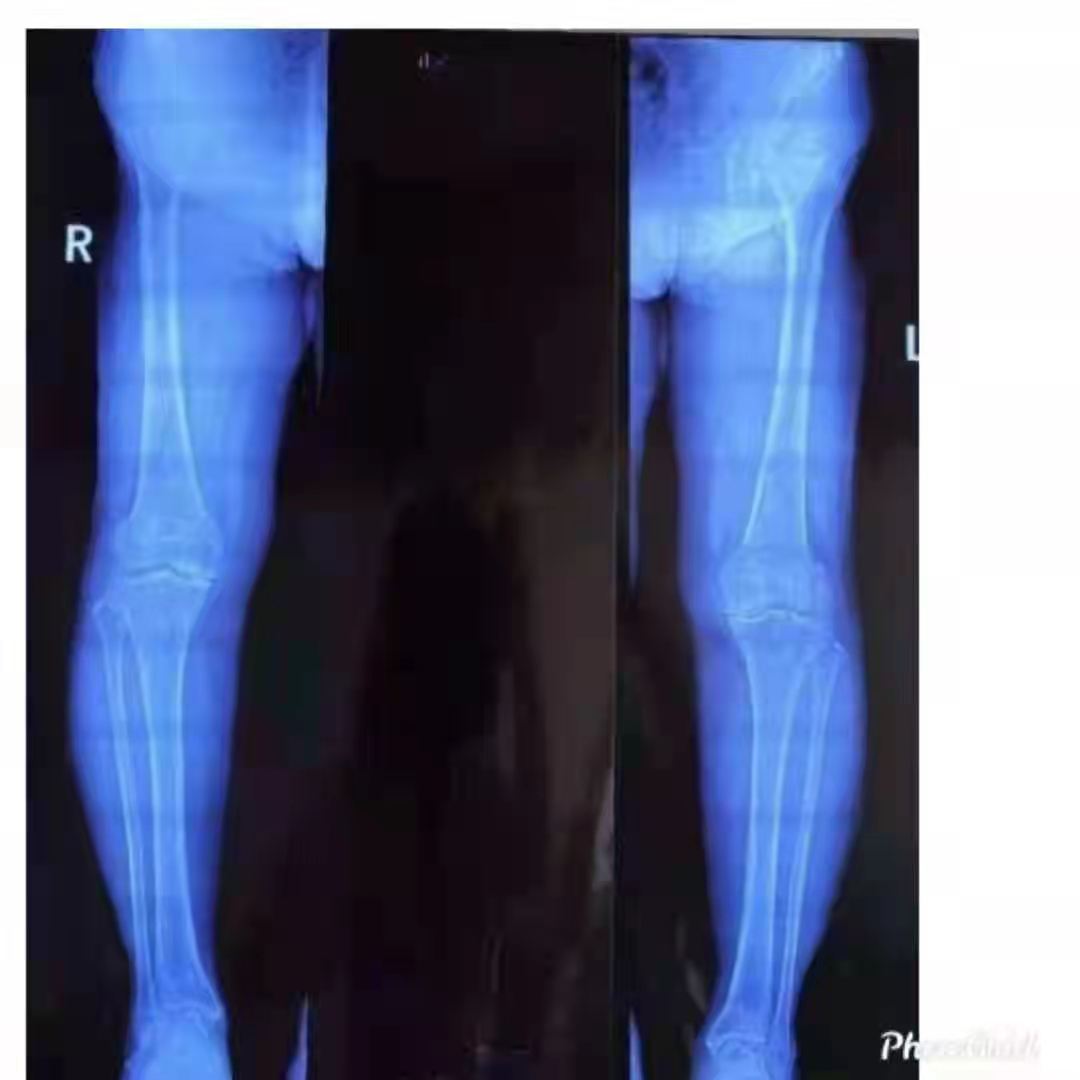

家住山亭區(qū)的王女士今年67歲。雙側(cè)膝關(guān)節(jié)疼痛多年,手術(shù)前已有加重現(xiàn)象,給生活帶來(lái)了很大不便。病魔帶來(lái)的痛苦讓他對(duì)未來(lái)失去了信心,農(nóng)活干不了,家務(wù)也不能操持,感覺(jué)自己像個(gè)廢人一樣。

幸運(yùn)的是,王女士慕名來(lái)到了山亭誠(chéng)德骨科醫(yī)院,專家檢查診斷,發(fā)現(xiàn)王女士雙側(cè)膝關(guān)節(jié)內(nèi)側(cè)磨損嚴(yán)重,外側(cè)部分和前后交叉韌帶上好,因此采取雙側(cè)同期部分置換。應(yīng)用牛津單髁活動(dòng)平臺(tái),手術(shù)屬于保膝范疇,保留了好的部分,修補(bǔ)了磨損重的部分,病人感受好,恢復(fù)快,功能好。如果錯(cuò)過(guò)這個(gè)修補(bǔ)的時(shí)機(jī),整個(gè)關(guān)節(jié)都磨損了,只能進(jìn)行全膝置換了。

術(shù)后,王女士恢復(fù)很好。疼痛癥狀完全消失,臉上也露出了久違的笑容。